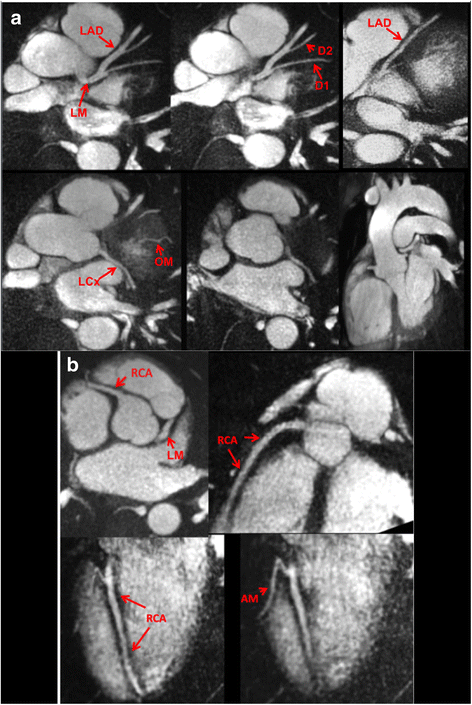

Background: Coronary magnetic resonance angiography (MRA) is usually obtained with a free-breathing navigator-gated 3D acquisition. Our aim was to develop an alternative breath-hold approach that would allow the coronary arteries to be evaluated in a much shorter time and without risk of degradation by respiratory motion artifacts. For this purpose, we implemented a breath-hold, non-contrast-enhanced, quiescent-interval slice-selective (QISS) 2D technique. Sequence performance was compared at 1.5 and 3 Tesla using both radial and Cartesian k-space trajectories.

Methods: The left coronary circulation was imaged in six healthy subjects and two patients with coronary artery disease. Breath-hold QISS was compared with T2-prepared 2D balanced steady-state free-precession (bSSFP) and free-breathing, navigator-gated 3D bSSFP.

Results: Approximately 10 2.1-mm thick slices were acquired in a single ~20-s breath-hold using two-shot QISS. QISS contrast-to-noise ratio (CNR) was 1.5-fold higher at 3 Tesla than at 1.5 Tesla. Cartesian QISS provided the best coronary-to-myocardium CNR, whereas radial QISS provided the sharpest coronary images. QISS image quality exceeded that of free-breathing 3D coronary MRA with few artifacts at either field strength. Compared with T2-prepared 2D bSSFP, multi-slice capability was not restricted by the specific absorption rate at 3 Tesla and pericardial fluid signal was better suppressed. In addition to depicting the coronary arteries, QISS could image intra-cardiac structures, pericardium, and the aortic root in arbitrary slice orientations.

Conclusions: Breath-hold QISS is a simple, versatile, and time-efficient method for coronary MRA that provides excellent image quality at both 1.5 and 3 Tesla. Image quality exceeded that of free-breathing, navigator-gated 3D MRA in a much shorter scan time. QISS also allowed rapid multi-slice bright-blood, diastolic phase imaging of the heart, which may have complementary value to multi-phase cine imaging. We conclude that, with further clinical validation, QISS might provide an efficient alternative to commonly used free-breathing coronary MRA techniques.